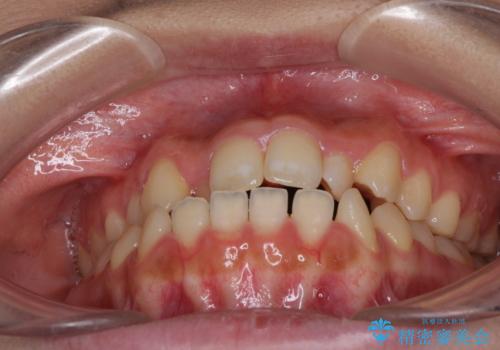

- 前歯のデコボコと、下顎の変位と受け口を気にして来院された患者様です。

初診時には大学病院にて顎の骨を切る外科矯正を勧めましたが、妥協的なゴールでも構わないので外科処置をせずに矯正を行いたいとのことでした。

まずは急速拡大装置にて上顎骨を側方に拡大し、インビザラインにて歯列と咬合を整えることとしました。